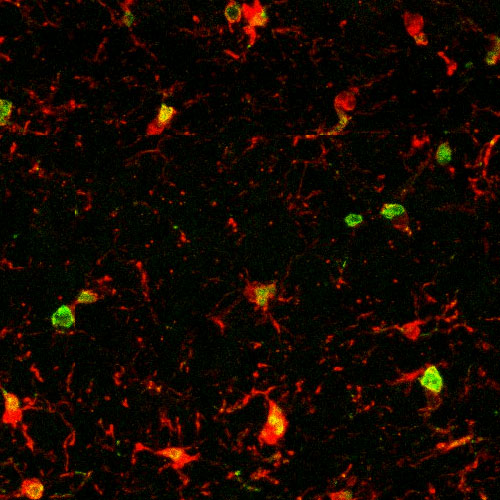

A microcopy showing microglia (red) in aged mice. Green and yellow areas in the microglia mark inflammation, which indicate aging.

This microscopic image shows microglia, immune cells in the brain, in red. The green and yellow areas point to age-related inflammation in an old mouse.